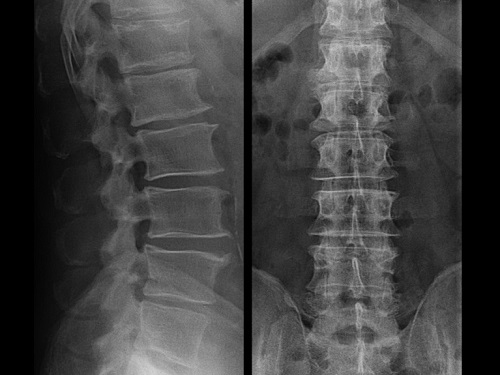

Тарским полицейским сообщили, что в больницу привезли 41-летнего мужчину с переломами позвоночника, ноги, ребра и травмой головы. По предварительным данным, пострадавший сорвался с дерева при заготовке ореха возле села Атирка. 31 августа пресс-служба омской полиции сообщила, что по данному факту проводится проверка.

Источник фото: artrozmed.ru